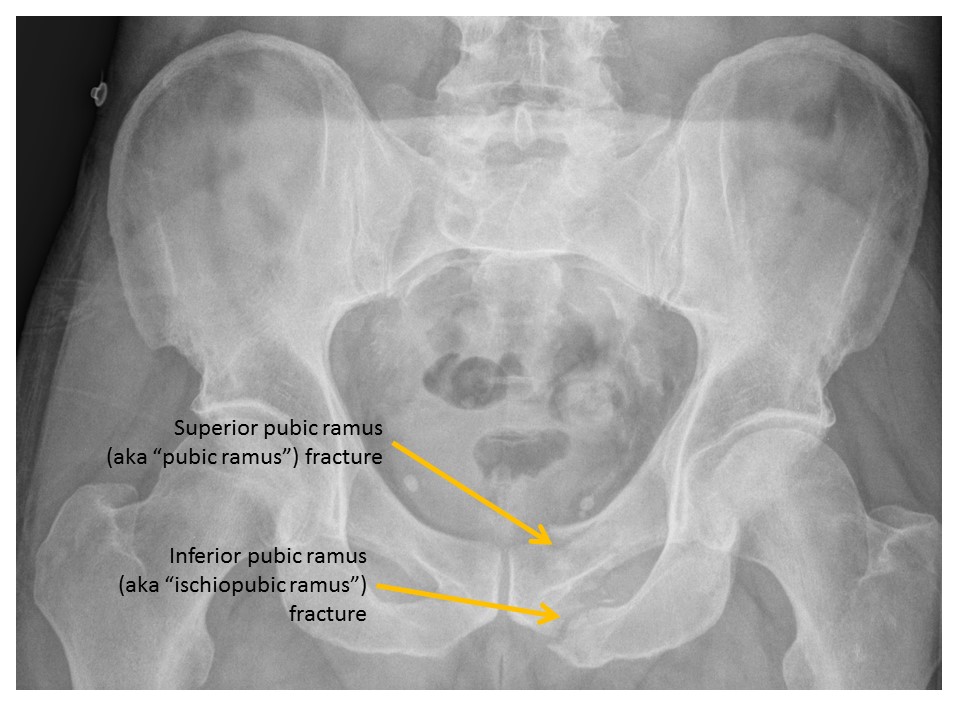

There is a pubic ramus fracture. |

Superior right hip dislocation with fracture of the posterior acetabular wall. A fracture of the femoral head with intra-articular body is also suspected.